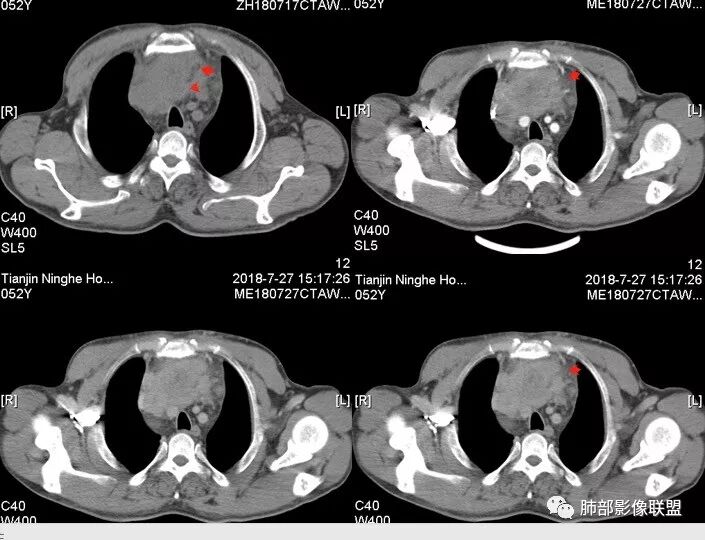

Yiren  Sishui(厶水伊人):上腔静脉受压后移,无侵犯,内乳动脉在其外侧,中心生长,定位纵隔,年龄>30岁,浅分叶,未见明显纤维分隔,其内见微钙化,坏死明显,周围脂肪间隙模糊,心包受累,考虑B3型胸腺瘤或胸腺癌.

大雄:中年男性,发现左前胸壁血管曲张1天入院肿标:细胞角蛋白19片段明显增高,神经元特异性烯醇化酶稍高CT:前纵膈巨大实性占位,边缘膨隆,质地较硬,纵膈脂肪间隙模糊,压迫纵膈大血管(头臂静脉明显狭窄)但未见包绕。平扫可见囊变及钙化,增强中度延迟强化,可见大片不规则坏死区。未见纵隔淋巴结肿大,胸骨骨质破坏及胸水。考虑:恶性肿瘤,胸腺癌可能。

水晶石头 (许建林):患者中年男性,因左前胸壁血管曲张1天就诊。查体左颈前胸壁、左上臂静脉曲张。血管彩超左颈内血静脉流淤滞。肿标:细胞角蛋白19片段明显增高,神经元特异性烯醇化酶稍高胸部CT:前纵隔巨大实性占位,边缘膨隆、清晰,纵隔脂肪间隙模糊,压迫纵隔大血管,未见包绕。平扫可见囊变及钙化,增强中度延迟强化,可见大片不规则坏死区。未见纵隔淋巴结肿大、胸骨骨质破坏及胸水。综合考虑恶性肿瘤,胸腺癌可能性大,鉴别恶性畸胎瘤。

崔少钢:中年男性,左侧颈内静脉、左侧前胸壁及左上臂静脉曲张,提示有静脉阻塞,另患者有恶性家族史。影像:前纵隔占位,有浅分叶,周围脂肪间隙不清晰,且见小淋巴结,内有坏死,上腔静脉受侵,内有钙化,支持胸腺癌。

南边:边界大部分清楚,有些地方毛糙。

上腔静脉如何?

心包如何?

大肿块,边缘不清,伴随肿大淋巴结,上腔静脉受侵犯——恶性